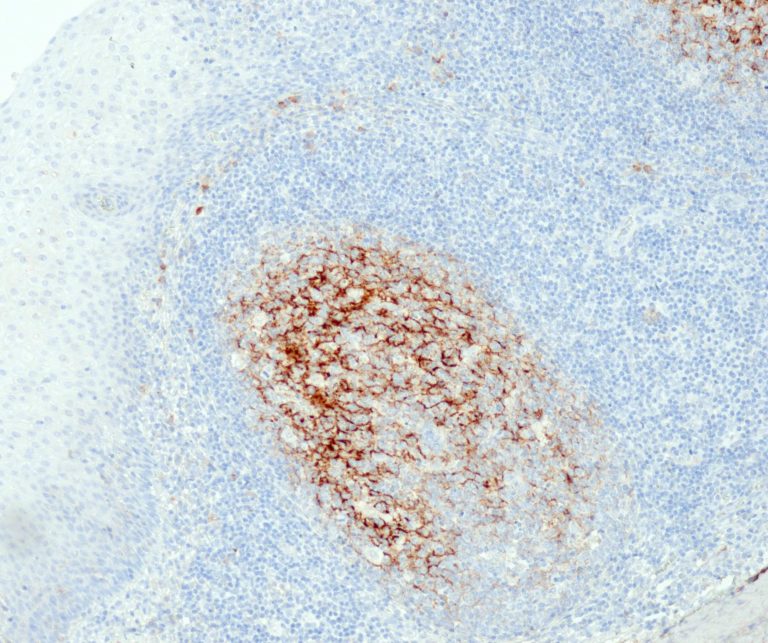

Hematopathology